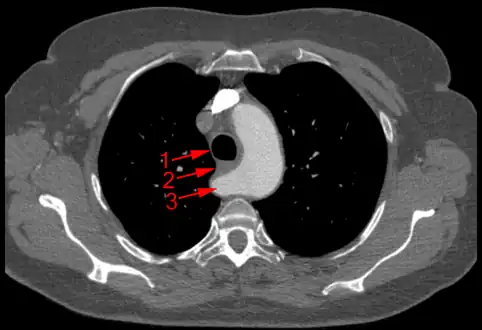

The evaluation of an aberrant subclavian artery can be done via CT angiography[7], which is a combo of CT scan with an injection of dye to produce images of blood vessels and/or tissues [8]

Aberrant subclavian artery at axial CT-scan. (1) trachea, (2) esophagus, (3) Aberrant subclavian artery.